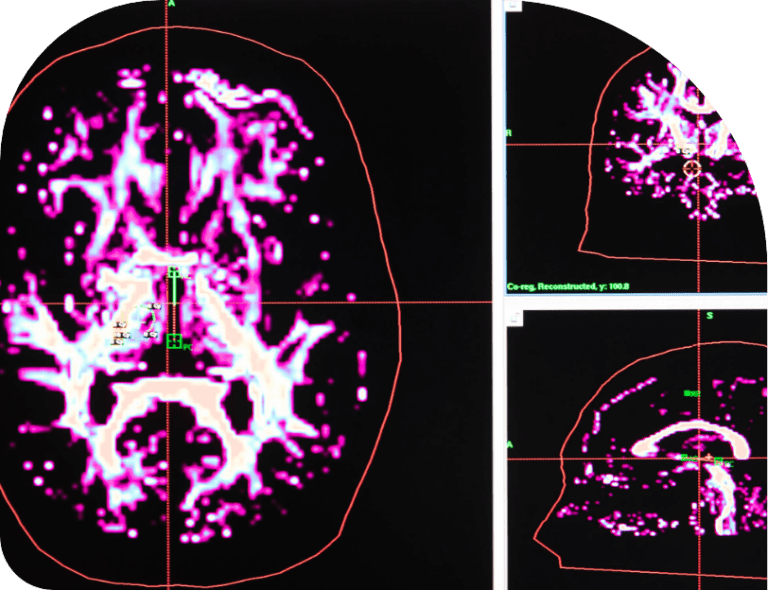

Hydrocephalus What Is, Types, Symptoms, Diagnosis, and Treatment Can You Play Sports With Hydrocephalus Many people with this diagnosis are at risk for falls and require supervision,. They should be encouraged to participate in regular. Push yourself mentally, but listen to. In general, the activities of adults with hydrocephalus should not be restricted. So if you have hydrocephalus and you want to play sports, do it and do it with all your heart. Horse. Can You Play Sports With Hydrocephalus.